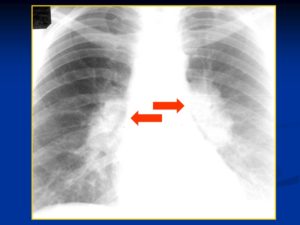

На рентгеновском снимке ограниченное затемнение легких в двух проекциях

Синдром круглой тени констатирую тогда, когда пятно на легких имеет круглую или овальную форму на двух выполненных перпендикулярно друг другу снимках, то есть спереди и сбоку. Для расшифровки результатов рентгенографии при обнаружении круглой тени опираются на 4 признака:

У данного пациента выявляется очаг в средней доле правом легком с полостью распада в центре (указано стрелкой). В соответствии с клиникой больному поставлен диагноз туберкулез.